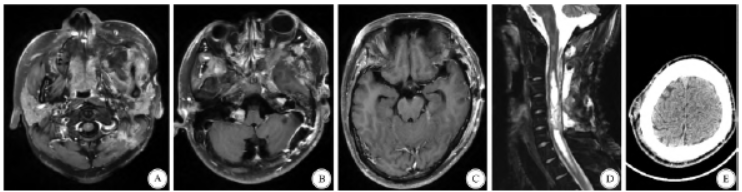

影像学检查提示患者颅内、翼腭窝、头皮下、颈、胸、腰及骶尾部散在占位(图1)。患者行3 次手术依次切除了左侧听神经瘤、左侧颞窝脑膜瘤、左侧翼腭窝区神经鞘瘤、C2 - 7髓内室管膜瘤、颈椎椎管内髓外神经鞘瘤及右侧颞顶枕部皮下神经鞘瘤(图2、图3)。术后病理结果显示左侧桥小脑角区、左侧翼腭窝、右侧颞顶枕部头皮下及颈椎管内髓外的肿瘤为神经鞘瘤,左侧颞窝肿瘤为脑膜瘤,颈椎管内髓内肿瘤为室管膜瘤。

图3 术后影像。全切除患者左侧翼腭窝神经鞘瘤、左侧听神经瘤、左侧颞窝脑膜瘤、颈髓内室管膜瘤、颈髓外神经鞘瘤及右侧颞顶枕部头皮下神经鞘瘤